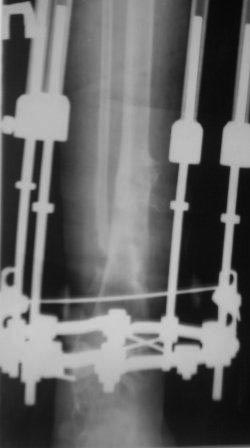

Контрольная Р-грамма на аппарате Илизарова после дистракции, теперь

видимо придется стабилизировать аппарат после устранения остаточных

деформаций.